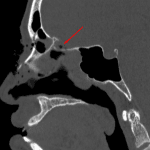

- Right globe rupture with internal and retrobulbar hemorrhage as well as right proptosis with stretched appearance of the optic nerve

- Acute complex right nasoorbitoethmoid fracture with comminuted fractures of the nasal arches, nasal septum, ethmoid air cell septae, medial orbital wall, and frontal sinus. There is likely also a nondisplaced cribriform plate fracture given trace pneumocephalus along the crista galli

- Acute right inferior and medial orbital wall blowout fractures with herniation of orbital fat through the orbital floor defect but no extraocular muscle herniation. There is, however, rounding of both inferior and medial rectus muscles. Notable involvement of the nasolacrimal canal and infraorbital foramen

- Right orbital floor fracture extends into the anterior wall of the maxillary sinus with multiple osseous fragments protruding into the sinus and associated hemosinus

Right globe rupture with internal and retrobulbar hemorrhage as well as right proptosis with stretched appearance of the optic nerve. Findings raise concern for optic nerve injury.

Acute complex right nasoorbitoethmoid fracture with comminuted fractures of the nasal arches, nasal septum, ethmoid air cell septae, medial orbital wall, and frontal sinus. There is likely also a nondisplaced cribriform plate fracture given trace pneumocephalus along the crista galli.

Acute right inferior and medial orbital wall blowout fractures with herniation of orbital fat through the orbital floor defect but no extraocular muscle herniation. There is, however, rounding of both inferior and medial rectus muscles. Recommend correlation with clinical signs of entrapment. Notable involvement of the nasolacrimal canal and infraorbital foramen.

Right orbital floor fracture extends into the anterior wall of the maxillary sinus with multiple osseous fragments protruding into the sinus and associated hemosinus.